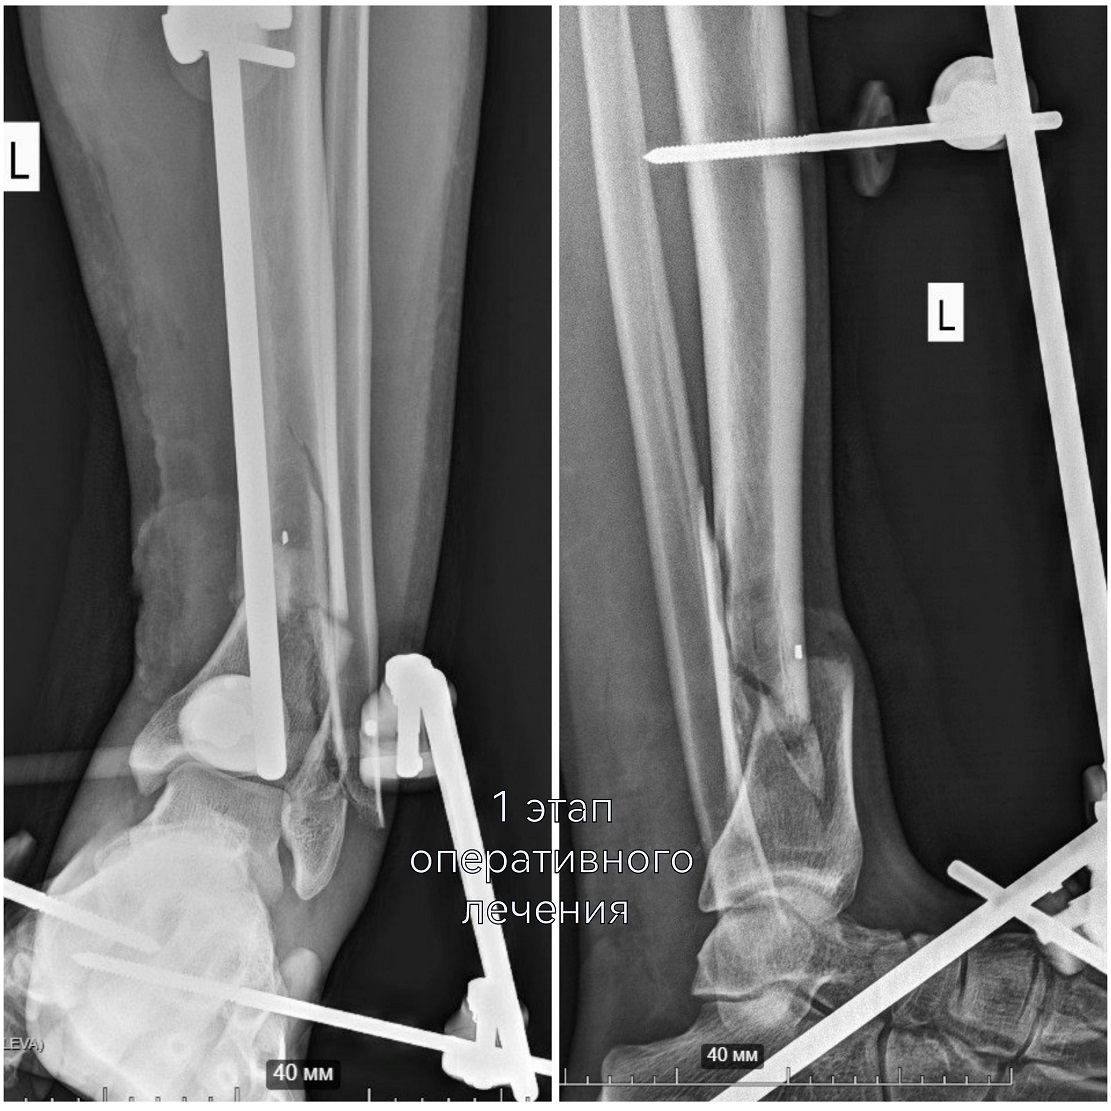

В экстренном порядке эффективно сработала команда опытных врачей травматологов-ортопедов Владимира Кельметра и Сергея Глиняного. На микрохирургическом этапе операции удалось восстановить целостность поврежденных сосудов и нервов. Кости голени зафиксировали с помощью модульной стрежневой системы.

Цель первого этапа хирургического лечения - жизнеспособность конечности – была достигнута. Цель второго этапа – опороспособность. К нему приступили, убедившись, что ранний послеоперационный период протекает благополучно, без осложнений.